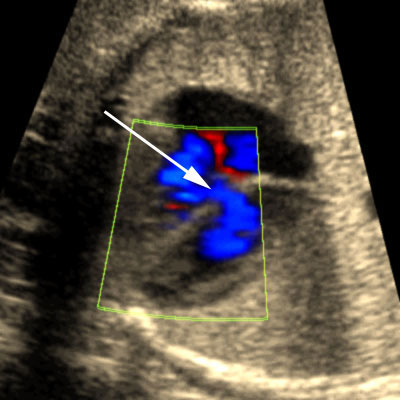

Color and pulsed Doppler of blood shunting across a muscular ventricular septal defect

Click the image to magnify it

Legend:Color and pulsed Doppler of blood shunting across a muscular ventricular septal defect

Reference(s):Paladini D, Palmieri S, Lamberti A, Teodoro A, Martinelli P, Nappi C. Characterization and natural history of ventricular septal defects in the fetus. Ultrasound Obstet Gynecol 2000;16(2):118–22. PubMed PMID: 11117079.

Axt-Fliedner R, Schwarze A, Smrcek J, Germer U, Krapp M, Gembruch U. Isolated ventricular septal defects detected by color Doppler imaging: evolution during fetal and first year of postnatal life. Ultrasound Obstet Gynecol 2006;27(3):266–73. PubMed PMID: 16485323.